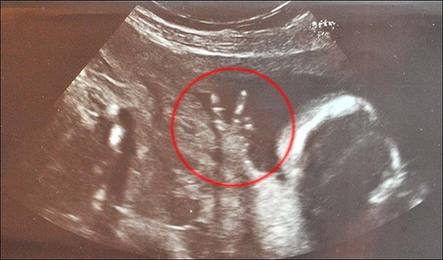

中國日報網(wǎng)環(huán)球在線消息: 這恐怕是世界上最自信狂野的寶寶——他(她)還在媽媽肚子里時就比出了完美的V字型手勢,仿佛在向世人宣稱:“嘿,我可就要來到世上了哦,準(zhǔn)備接招吧各位!”

據(jù)英國《太陽報》7月9日報道,懷孕已經(jīng)23周的英國女子卡洛琳?巴恩斯近日來到醫(yī)院做定期的超聲波檢查,結(jié)果發(fā)現(xiàn)肚子里的寶寶居然從始至終都豎著兩根小手指頭,擺出了絕對到位的V字型手勢。